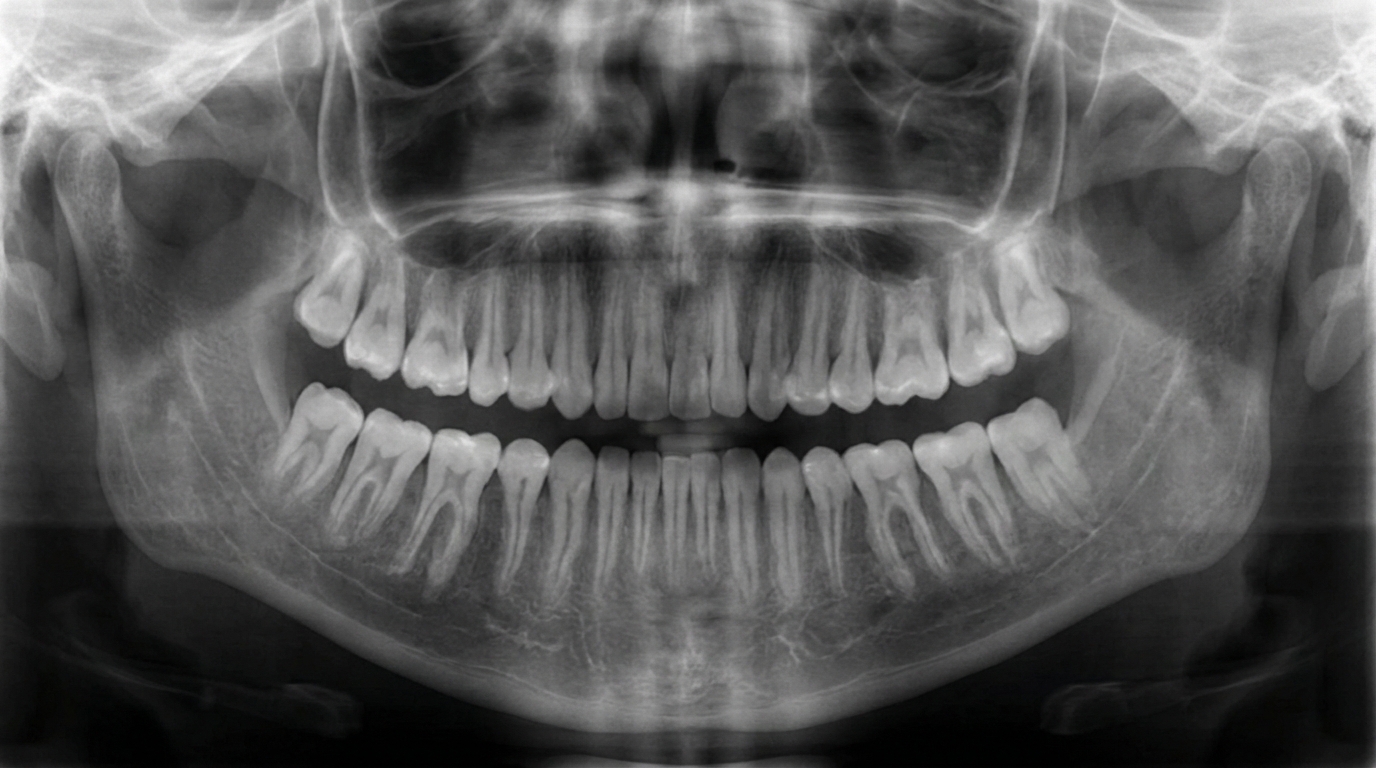

Grâce à nos équipements numériques (DIGORA, CEREC, OPT), nous réalisons des radiographies et des empreintes dentaires d’une grande précision, tout en assurant le confort du patient.

Nos systèmes de radiologie numérique permettent un diagnostic rapide et fiable, tout en réduisant considérablement la dose de rayonnement.

Ils offrent une visualisation des dents, des racines et de l’os, facilitant la détection des caries, infections, fractures ou kystes, et améliorant la planification des traitements.

Nos systèmes de radiologie numérique permettent un diagnostic rapide et fiable, tout en réduisant considérablement la dose de rayonnement. Ils offrent une visualisation des dents, des racines et de l’os, facilitant la détection des caries, infections, fractures ou kystes, et améliorant la planification des traitements.